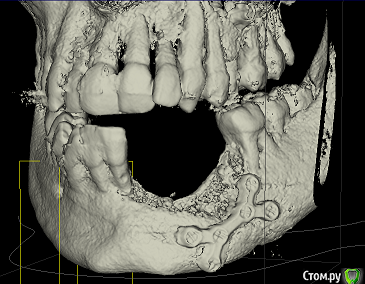

mikheil.osipov Опубликовано 18 декабря, 2015 Автор Поделиться Опубликовано 18 декабря, 2015 Спасибо Вам за отзывы. А в чем заключается сложность с гигиеной в этом случае? Зубы будут сниматься с имплантов и их надо будет чистить как протез?Сколько имлантов можно установить без костной пластики и приблизительно как долго они мне праслужат? Мне сказали что без наращивания кости можно установить только два импланта и с ними надо будет аккуратно оброщаться, а в случае наращивания поставят три, а на них мост. Меня волнует наращивание кости, ведь процедура не простая и нужно время чтобы все срослось, есть определенные риски. Конечно, востановить утраченную кость будет отлично, но всеже поскажите какие приемушества мне даст костная пластика? Как поведет себя зубной ряд и челюсть со временем если оставить такой дефект и прямо поставить импланты? Как долго продержится первый зуб? Также меня интересует вопрос пластины. Мой врачь говорит, что кость приросла к винтам и снимать ее нельзя, хотя некоторые врачи говорять что снимать нужно после того как кость срастется. В интернете тоже разные мнения по эмоту вопросу. Мне всеже хотелось бы снять ее, ведь после сростания она будет не нужна и со временем может создать проблемы. К тому же верхний край пластины просвечивается через слизистую. Что вы считаете по этому поводу? Можно ли снять пластину и можно ли совместить это с костной пластикой? И еще, нужно ли удалять шов с верхней челюсти? Вот еще снимок с 3Д: Спасибо заранее! Ссылка на комментарий

ILGAMSA Опубликовано 19 декабря, 2015 Поделиться Опубликовано 19 декабря, 2015 Весь вопрос в том, согласны ли Вы будете на компромиссное решение проблемы? Если нарастить и кость, и десну, установить имплантаты в правильной позиции, то в последующем Вы будете относиться к коронкам на имплантатах как к своим зубам, без чрезмерного акцента к аспекту гигиены и контрольных осмотров у стоматолога.Я за наращивание костной ткани.Пластину можно снять в момент наращивания.Сделать это можно и так: http://s019.radikal.ru/i634/1512/2b/780dadd4a19c.jpg 4 Ссылка на комментарий

ILGAMSA Опубликовано 20 декабря, 2015 Поделиться Опубликовано 20 декабря, 2015 Пластика десны это лоскут с неба, да. Как правило, её можно делать после интеграции иимплантатов. На фото сэндвич-техника. Сверху аутокость, посередине животного происхождения.Операцию можно проводить как под местной, так и общей анестезией.Если делать по этой методике, как на фото, то после костной пластики через 4 месяца можно устанавливать имплантаты, еще 3 месяца на их интеграцию, затем пластика мягких тканей, через 1 месяц изготовление временных коронок.Удалить 8 зуб можно как под местной, так и общей анестезией. 1 Ссылка на комментарий